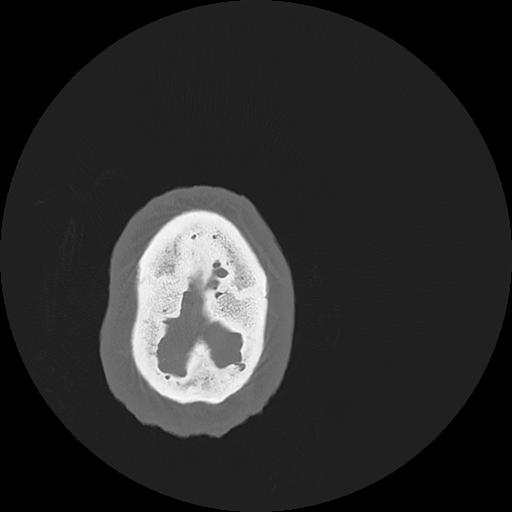

7 HUESO,,Vol,0.5,HUESO,,